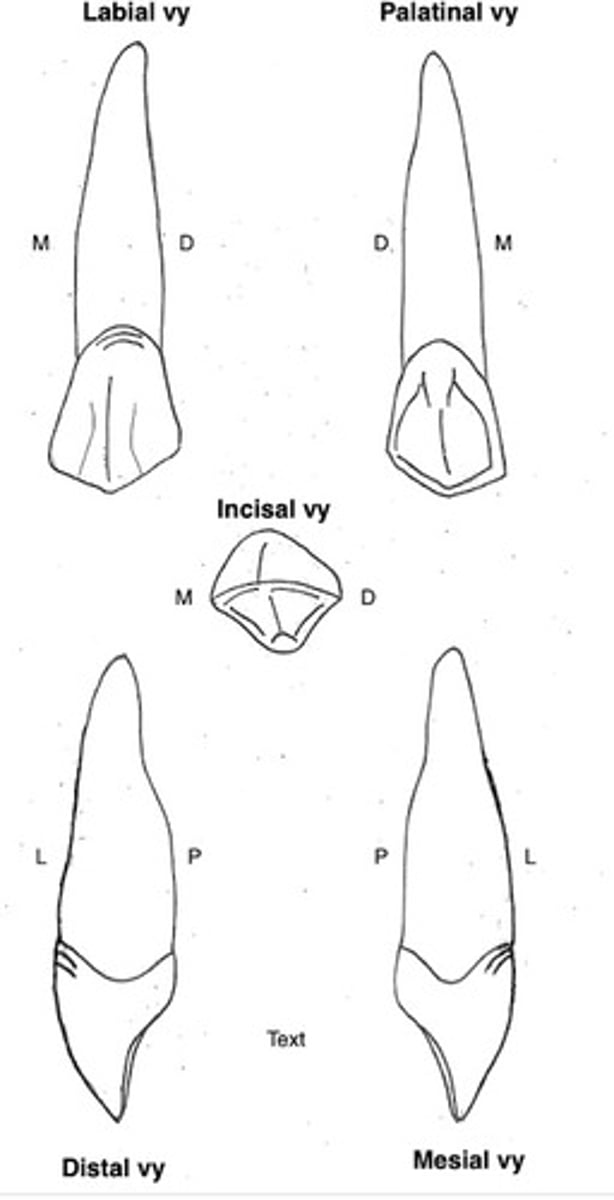

Överkäkens första premolar (14 och 24)

Kronans form

- två kuspar

- Buckala kuspen är oftast lite högre än den palatinala

- assymetrisk "yttre" form

- konkav mesialyta

- omvänt böjningstecken (dvs är 14 och 24 buckala yta mer prominent distalt åt)

Storlek:

- större än överkäkens övriga premolarer

Övrigt:

Oftast tvådelad rotspets